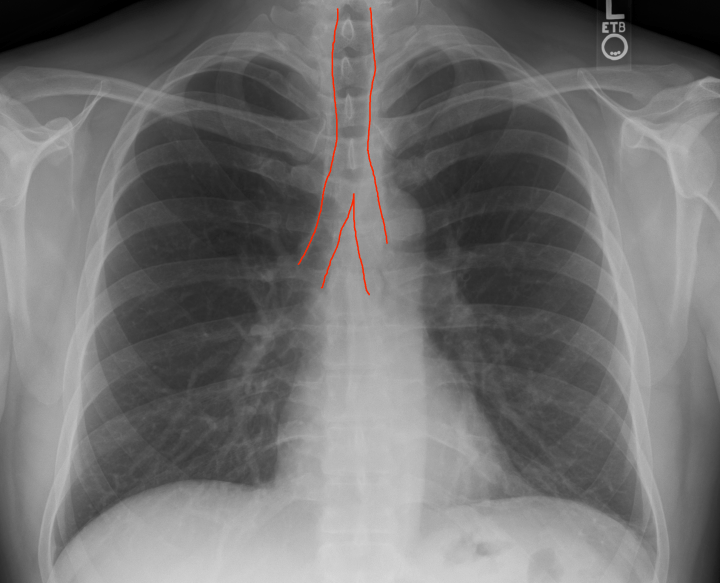

- Rotation: Look at the sternoclavicular joint (where you clavicle meets your breast bone). There should be equal spacing when comparing the left and right. If one side has greater gapping, that patient is rotated to that side and is not truly perpendicular to the imager. While this doesn’t seem like a big deal a rotation will distort the view of the heart & mediastinum potentially leading to a false diagnosis of cardiomegaly and/or widened mediastinum. Not good. I would dictate this as “non-rotated or neutral rotation”.